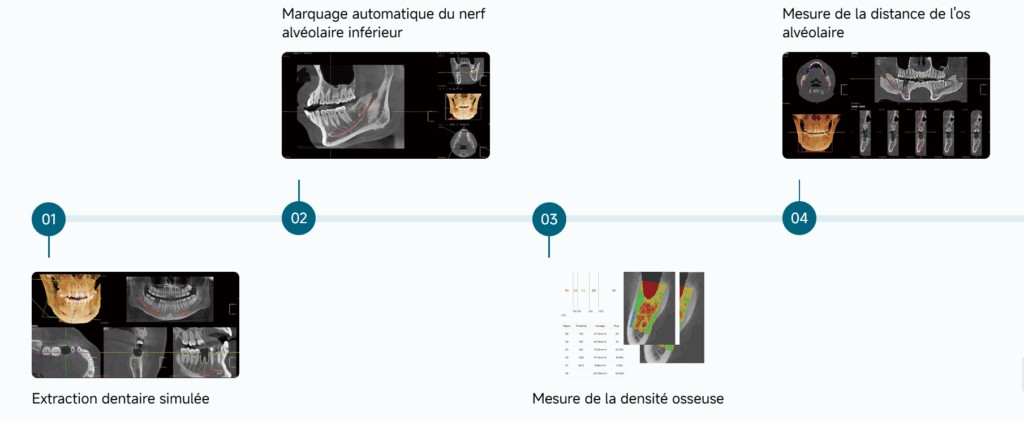

Votre puissant assistant IA

Solution implantaire tout-en-un

L’amélioration de la sécurité et de l’efficacité des interventions chirurgicales d’implants facilite la communication entre le médecin et le patient.